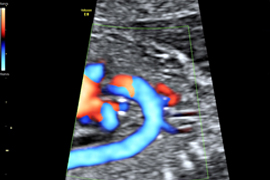

Herz-Ultraschall (Echokardiographie)

Farbdoppler

Durch eine sehr spezielle Ultraschalluntersuchung können die kindlichen Organe eingehend untersucht werden. Hierbei wird ihre Struktur dargestellt und die Funktion (z.B. des kindlichen Herzens) überprüft. Eine Vielzahl von leichten und schweren Entwicklungsstörungen können hierbei ausgeschlossen werden.

Bei der fetalen Echokardiographie (Herz-Ultraschall) wird das Herz bis ins Detail dargestellt und untersucht (Wände, Kammern, Klappen, Blutgefäße und die Beweglichkeit des Herzens); hierfür wird zusätzlich die farbkodierte Dopplersonographie angewandt, welche die Blutflussrichtung sichtbar macht.